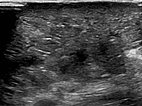

B-scan ultrasonography of the subcutaneous portion of the lymphatic malformation shows a dysplastic dilated lymphatic duct as an anechoic tubular structure. The surrounding subcutaneous adipose tissue is clearly more echogenic than normal due to the interspersed lymphatic fluid.

B-scan ultrasonography (cross-section of proximal ventral thigh) also shows the clearly echogenic tissue, interspersed with individual very fine, dilated, fluid-filled lymphatic ducts.